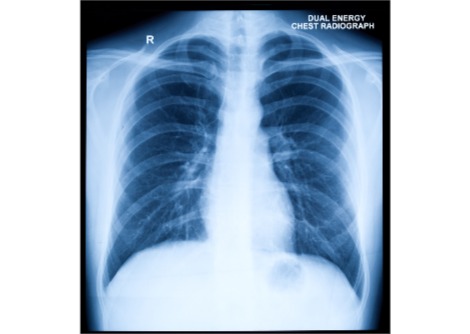

تتأثر آلام أسفل الظهر بالعديد من العوامل ، بما في ذلك البيولوجية والاجتماعية والنفسية . يعني التعقيد التشريحي للعمود الفقري البشري أنه في معظم الحالات ، لا يمكن تحديد سبب بنيوي بسيط مثل مفصل أو عضلة واحدة ، حتى مع التصوير التشخيصي المتطور.

هذا يعني أن التشخيص يتم إلى حد كبير على أساس الأعراض المبلغ عنها  . وعلى الرغم من أن معظم حالات آلام أسفل الظهر قصيرة الأجل ، مع التعافي خلال الأسابيع الستة الأولى من ظهور الألم ، فإن ثلث الحالات ستصبح مستمرة وقد تستمر لسنوات. استمرار الألم يساهم  في العبء الكبير لهذه الحالة .